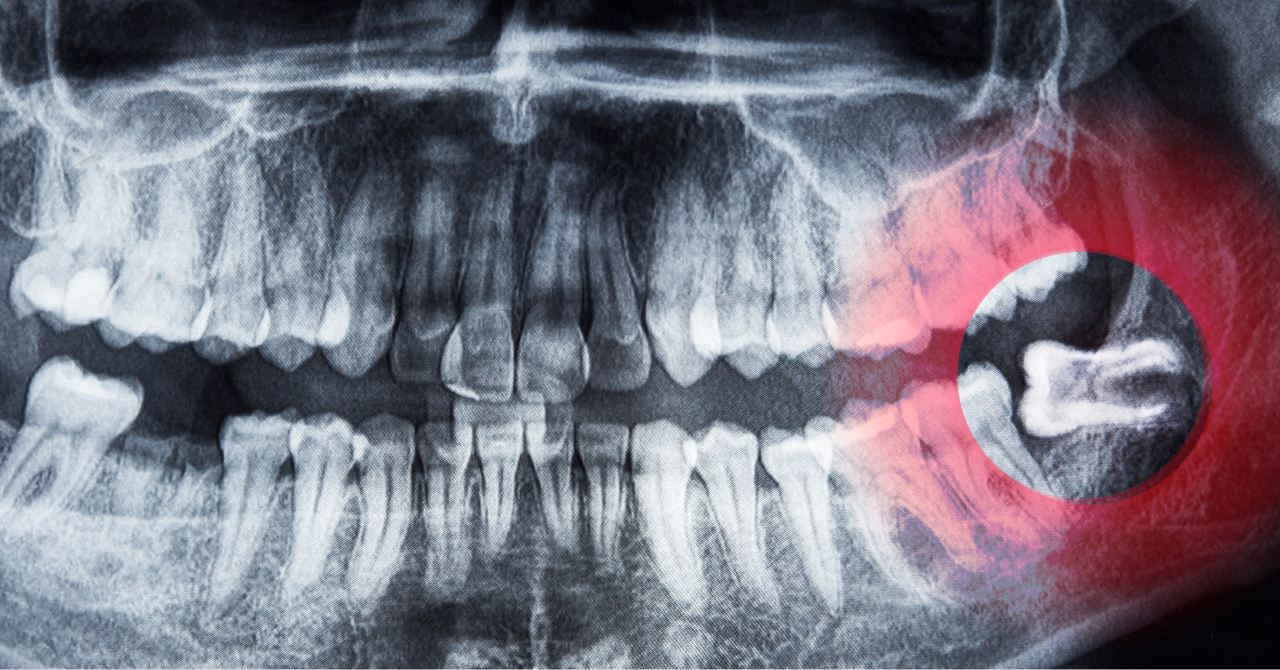

特に、親知らずの抜歯や顎関節症の診断・治療など、一般の歯科医院では対応が難しい症例にも柔軟に対応可能です。

親知らずの生え方や位置によっては、放置すると周囲の歯列や顎に悪影響を及ぼすことがあり、専門的な判断が必要です。

同院ではCTによる三次元的な画像診断を用い、安全性と正確性を重視した治療を行っています。